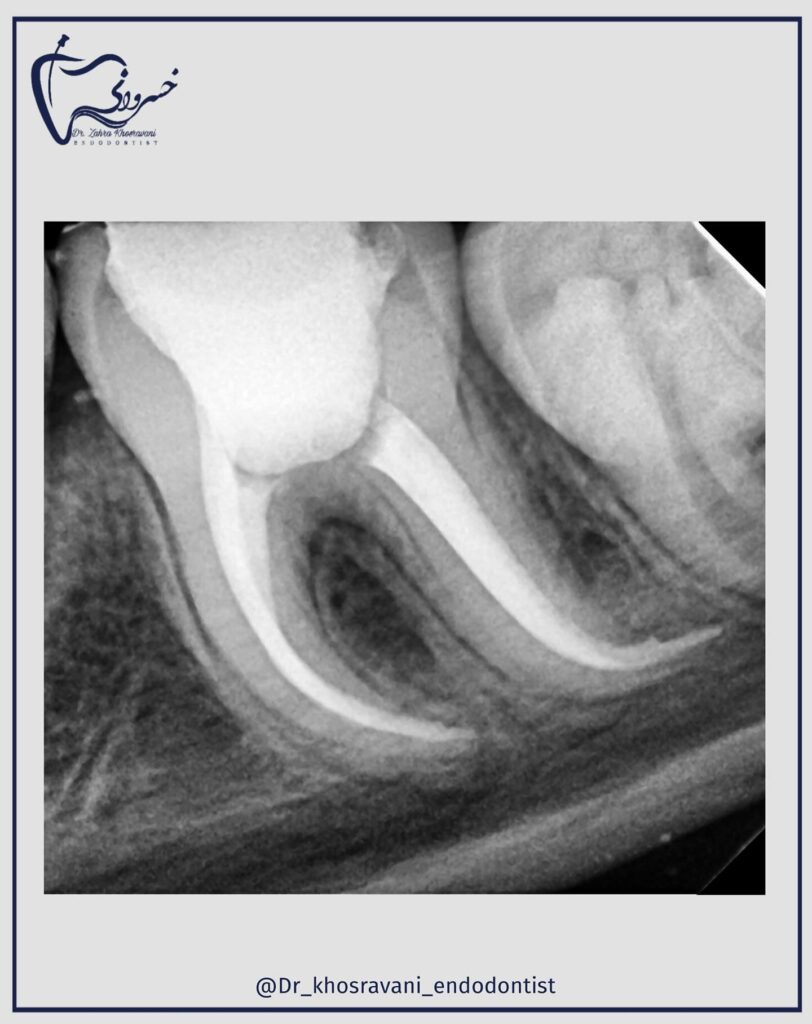

درمان ریشه مجدد

درمان ریشه مجدد دندان مولر دوم با ریشه رادیکس